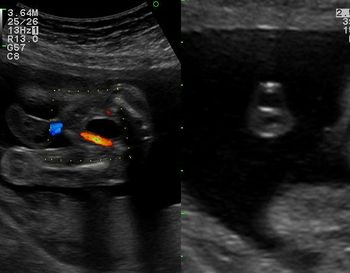

Single umbilical artery color doppler, transverse scan of urinary bladder shows single umbilical artery (left), transverse section of umbilical cord showing only two vessels: one vein and one artery (right).